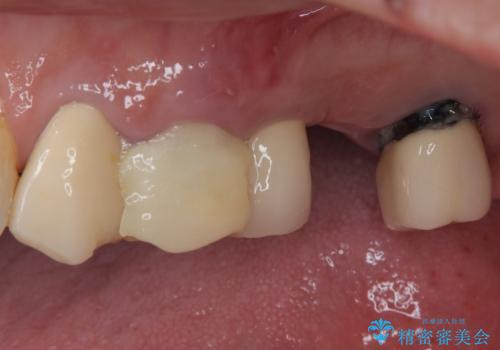

- 抜歯が必要と言われ、インプラント治療を希望して来院された患者様です。

歯がボロボロで抜歯が必要な状態であり、後方にはインプラントが埋入されているため、同様にインプラントによる補綴治療を行うこととしました。

クラウンを装着できないため、プラスチックを歯に流し込んで仮歯のようにしている状態でした。